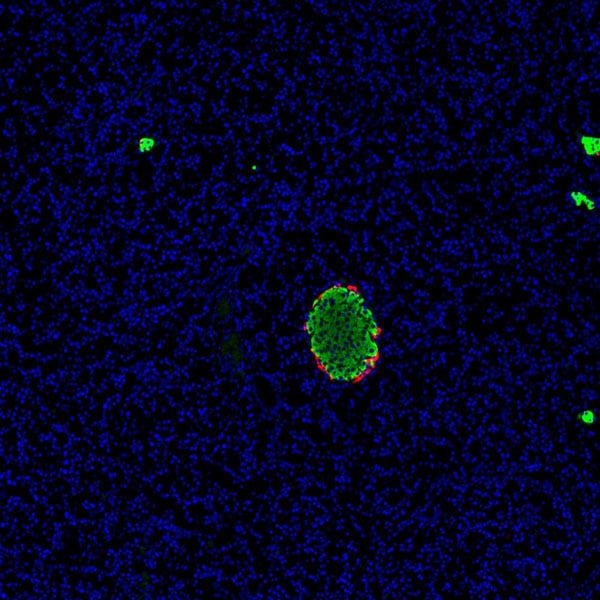

IF (Immunofluorescence)

(Immunofluorescence analysis of paraffin-embedded Rat pancreas using GCG Polyclonal Antibody at dilution of 1:200.Red is labeled with glucagon antibody and green is labeled with insulin antibody.)